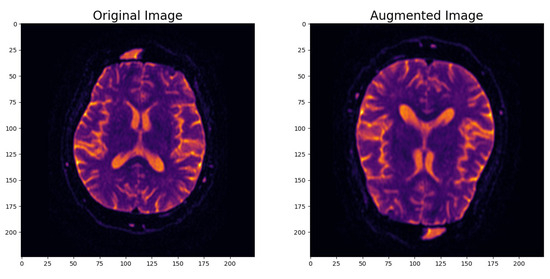

- Image Data Augmentation: To enhance the model’s robustness and its ability to generalize effectively, we introduced an image data augmentation layer. This layer applied random horizontal and vertical flips as well as zooming to the images. The augmentation process simulated real-world variations in MRI scans and introduced variability into the dataset. As shown in Figure 2, this data augmentation process effectively transformed the original images, enhancing the dataset’s diversity and introducing the necessary variability for robust model training.

Figure 2. Example of augmented image. - Input Data Pipeline with the tf.data API: To create a streamlined and efficient input data pipeline, we leveraged the TensorFlow ‘tf.data’ API. Table 1 provides an overview of the key components within the input data pipeline, emphasizing their roles in optimizing data processing for model training and evaluation.